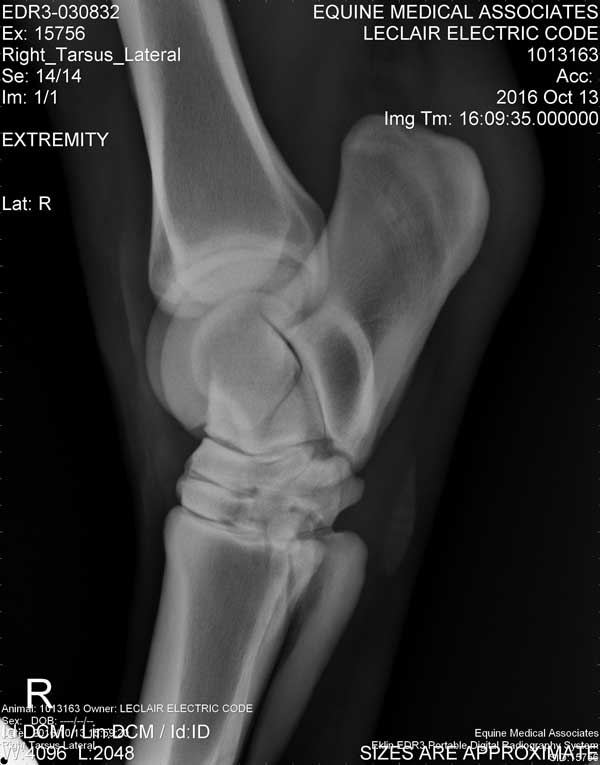

Electric Code is 11 years old at the time these X-Rays were taken on October 13, 2016

Hock/Tarsal

Right